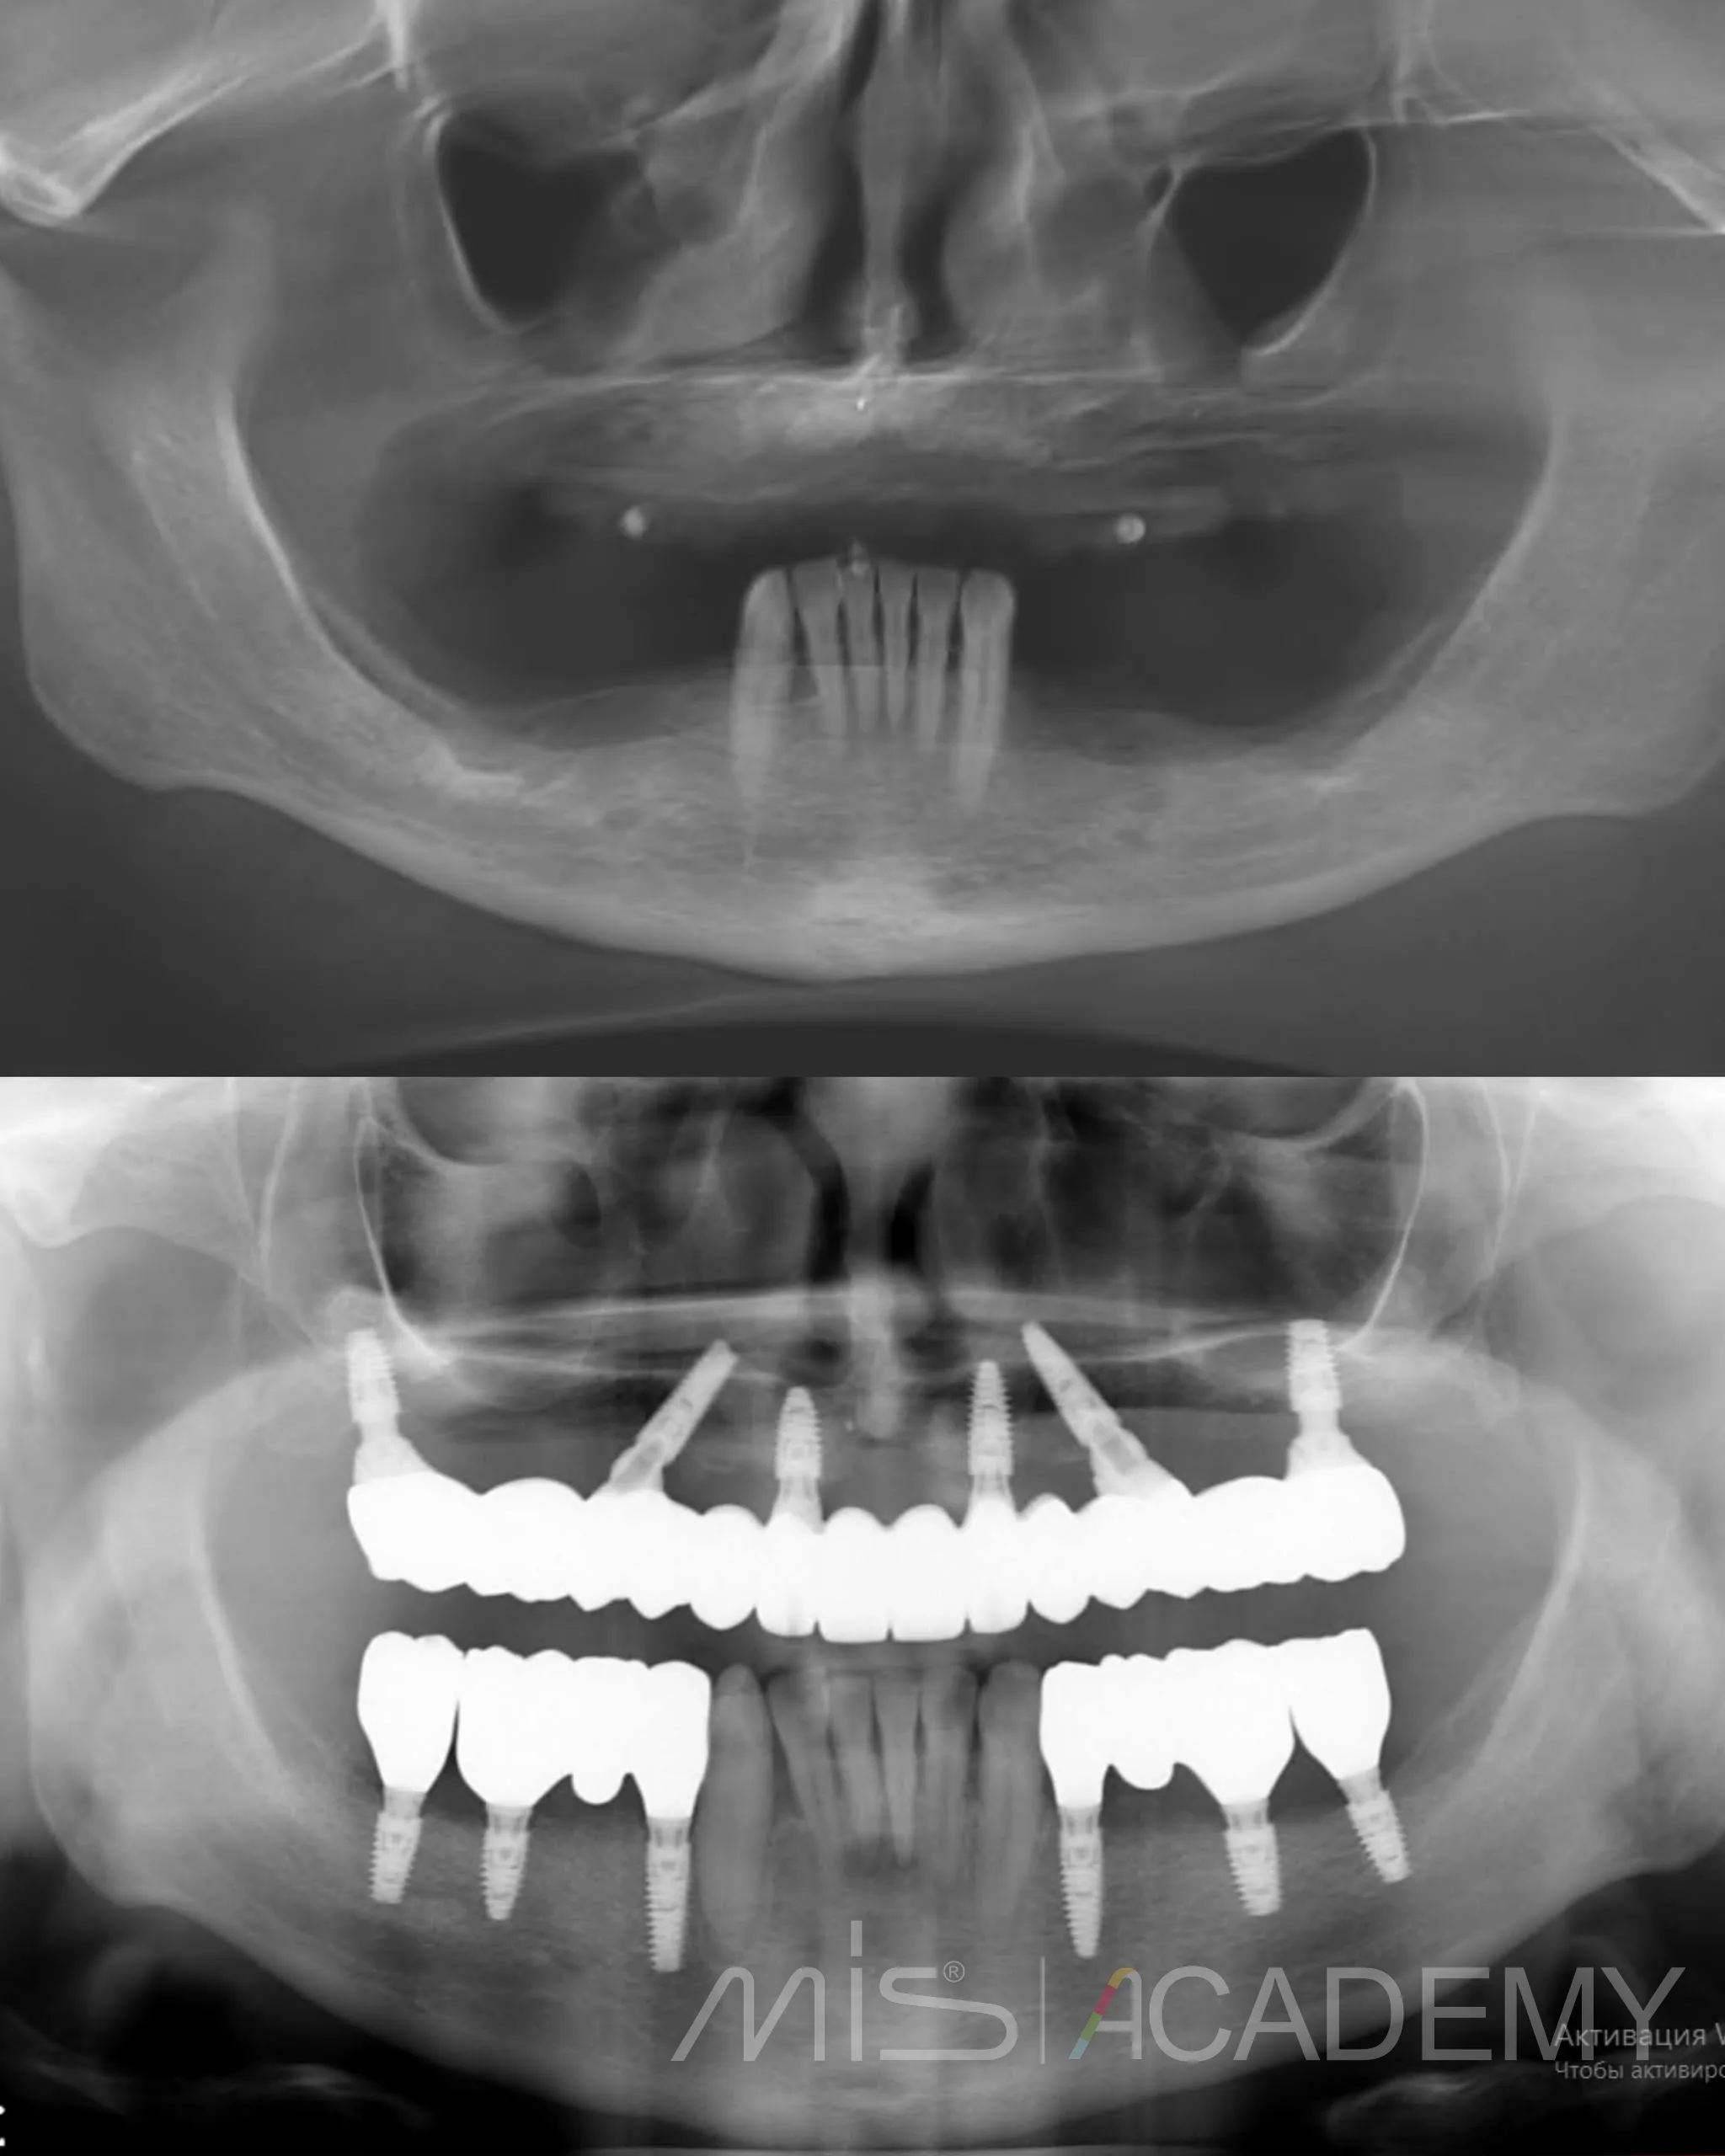

Комплексная реабилитация пациента 38 лет.

В анамнезе неудачное лечение зубов, приведшее к их удалению. В предыдущей клинике удалили все несостоятельные зубы, рекомендовали подождать 6 месяцев с временными протезами, после чего на контрольном КТ костной ткани для имплантации не увидели и на этом лечение фактически закончилось.

Пациент обратился к нам. Совместно с Игорем Лёвушкиным составили пошаговый план реабилитации.

— По навигационному накостному шаблону установили 6 имплантатов MIS C1.

— В дистальных отделах выполнены открытый и закрытый синуслифтинги под заглушки.

— Установлены имплантаты MIS C1.

— Костная пластика материалами Osteobiol: справа ксено MP3 с Derma, слева Gen-Os с нативным коллагеном и Lamina Curved, ушивание.